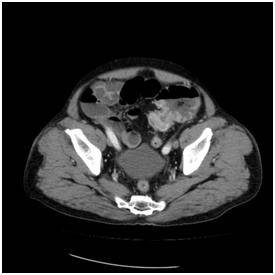

![대장암으로 장폐쇄가 생겨서 유발된 변비 [서울대병원 제공]](https://img4.daumcdn.net/thumb/R658x0.q70/?fname=https://t1.daumcdn.net/news/202507/30/yonhap/20250730061502859ngyz.jpg)

최악의 대장·항문질환 '대장암'…50세 이후 대장내시경 필수

노년기 대장·항문질환 중 가장 위험한 건 대장암이다. 대장암은 1990년 후반 이후 현재까지 우리나라에서 급격히 증가하고 있는 암이다. 해마다 국내 암 발생률 2∼3위에 오르고 있다.

정 이사장은 "대장암은 초기 증상이 거의 없기 때문에 대장내시경만이 유일한 조기 진단 방법이자 즉시 제거할 수 있는 치료 수단"이라며 "대장암은 조기(1, 2기)에 발견하면 90% 이상이 완치할 수 있지만 고령층에서는 출혈이나 변비 등의 전형적인 증상보다 묵직함, 복통, 빈혈 등 비특이 증상으로 나타나기 때문에 각별한 주의가 필요하다"고 말했다.